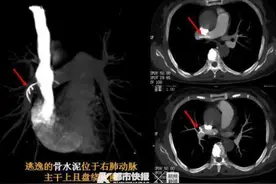

2020年10月20日上午原告张某芬因自己的腰部受伤于当天下午3点半左右自行去被告处治疗,于当天住院,2020年10月21日下午4点动的手术手术者是凌某伟,助手是郭某,手术中原告就自感心脏不适,心内有推击声,术后感觉胸闷不适,手术进行69分钟。